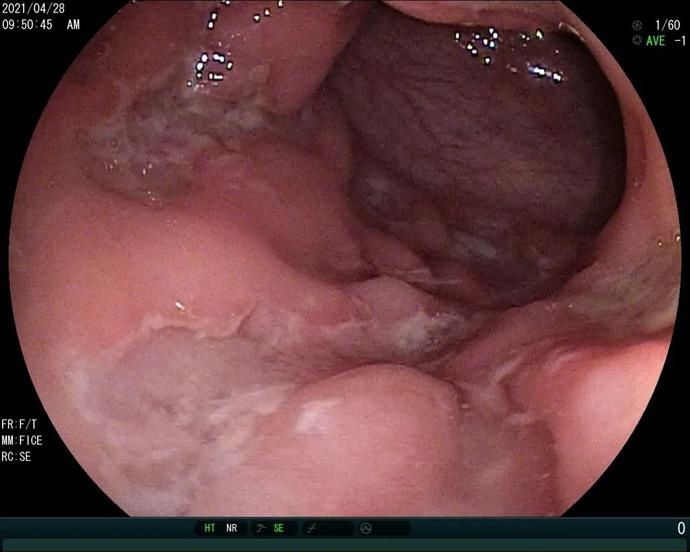

炎症性肠病(inflammatory bowel disease, IBD)是指病因不明的一组非特异性肠道炎性疾病。极早发性炎症性肠病(VEO-IBD)是指在6岁以前发病并诊断的IBD。VEO-IBD以发病年龄早、起病重、腹泻难控制、严重影响生长发育、多伴严重肛周病变、部分是基因缺陷所引起的遗传病为特点。结肠镜下表现为全结肠炎、黏膜鹅卵石样改变、深大溃疡等等。

宝宝被转到了上海瑞金医院,肖园安排宝宝做了血液、消化内镜等检查以及相关基因检测。检查结果提示:宝宝肠道内遍布大量深大溃疡、同时伴有严重的低蛋白血症,血清IL10水平明显升高,根据瑞金医院既往的研究和临床经验,临床基本上确诊为IL10RA缺陷。

原女士的宝宝肠道内的溃疡

此时如果肠镜出现全结肠累积、深大纵行溃疡就要重点考虑,如果实验室检查还发现IL10明显升高(瑞金经验>33.05 pg/ml)就可以临床确诊了。